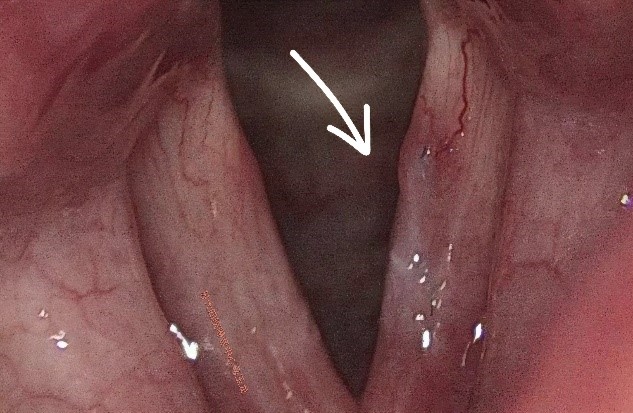

考虑到传统剥脱术式,形成瘢痕的风险较大,术后声音嘶哑风险高,马玉龙副主任医师决定采用“显微镜下声带黏膜缝合技术”为刘女士进行嗓音手术,精准切除水肿组织,最大限度恢复声带振动功能。术后,我院耳鼻咽喉科医疗团队指导刘女士积极恢复,结合禁声管理、呼吸训练,降低粘连风险。1月后,刘女士及家人,专程从上海回苏州复查,声带黏膜恢复良好,嗓音恢复洪亮。